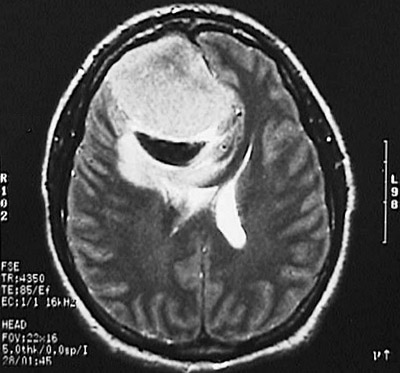

This T2 weighted MRI scan in axial view demonstrates a meningioma in the parasagittal region which is so large that it compresses the underlying cerebral hemisphere and impinges upon the lateral ventricle.